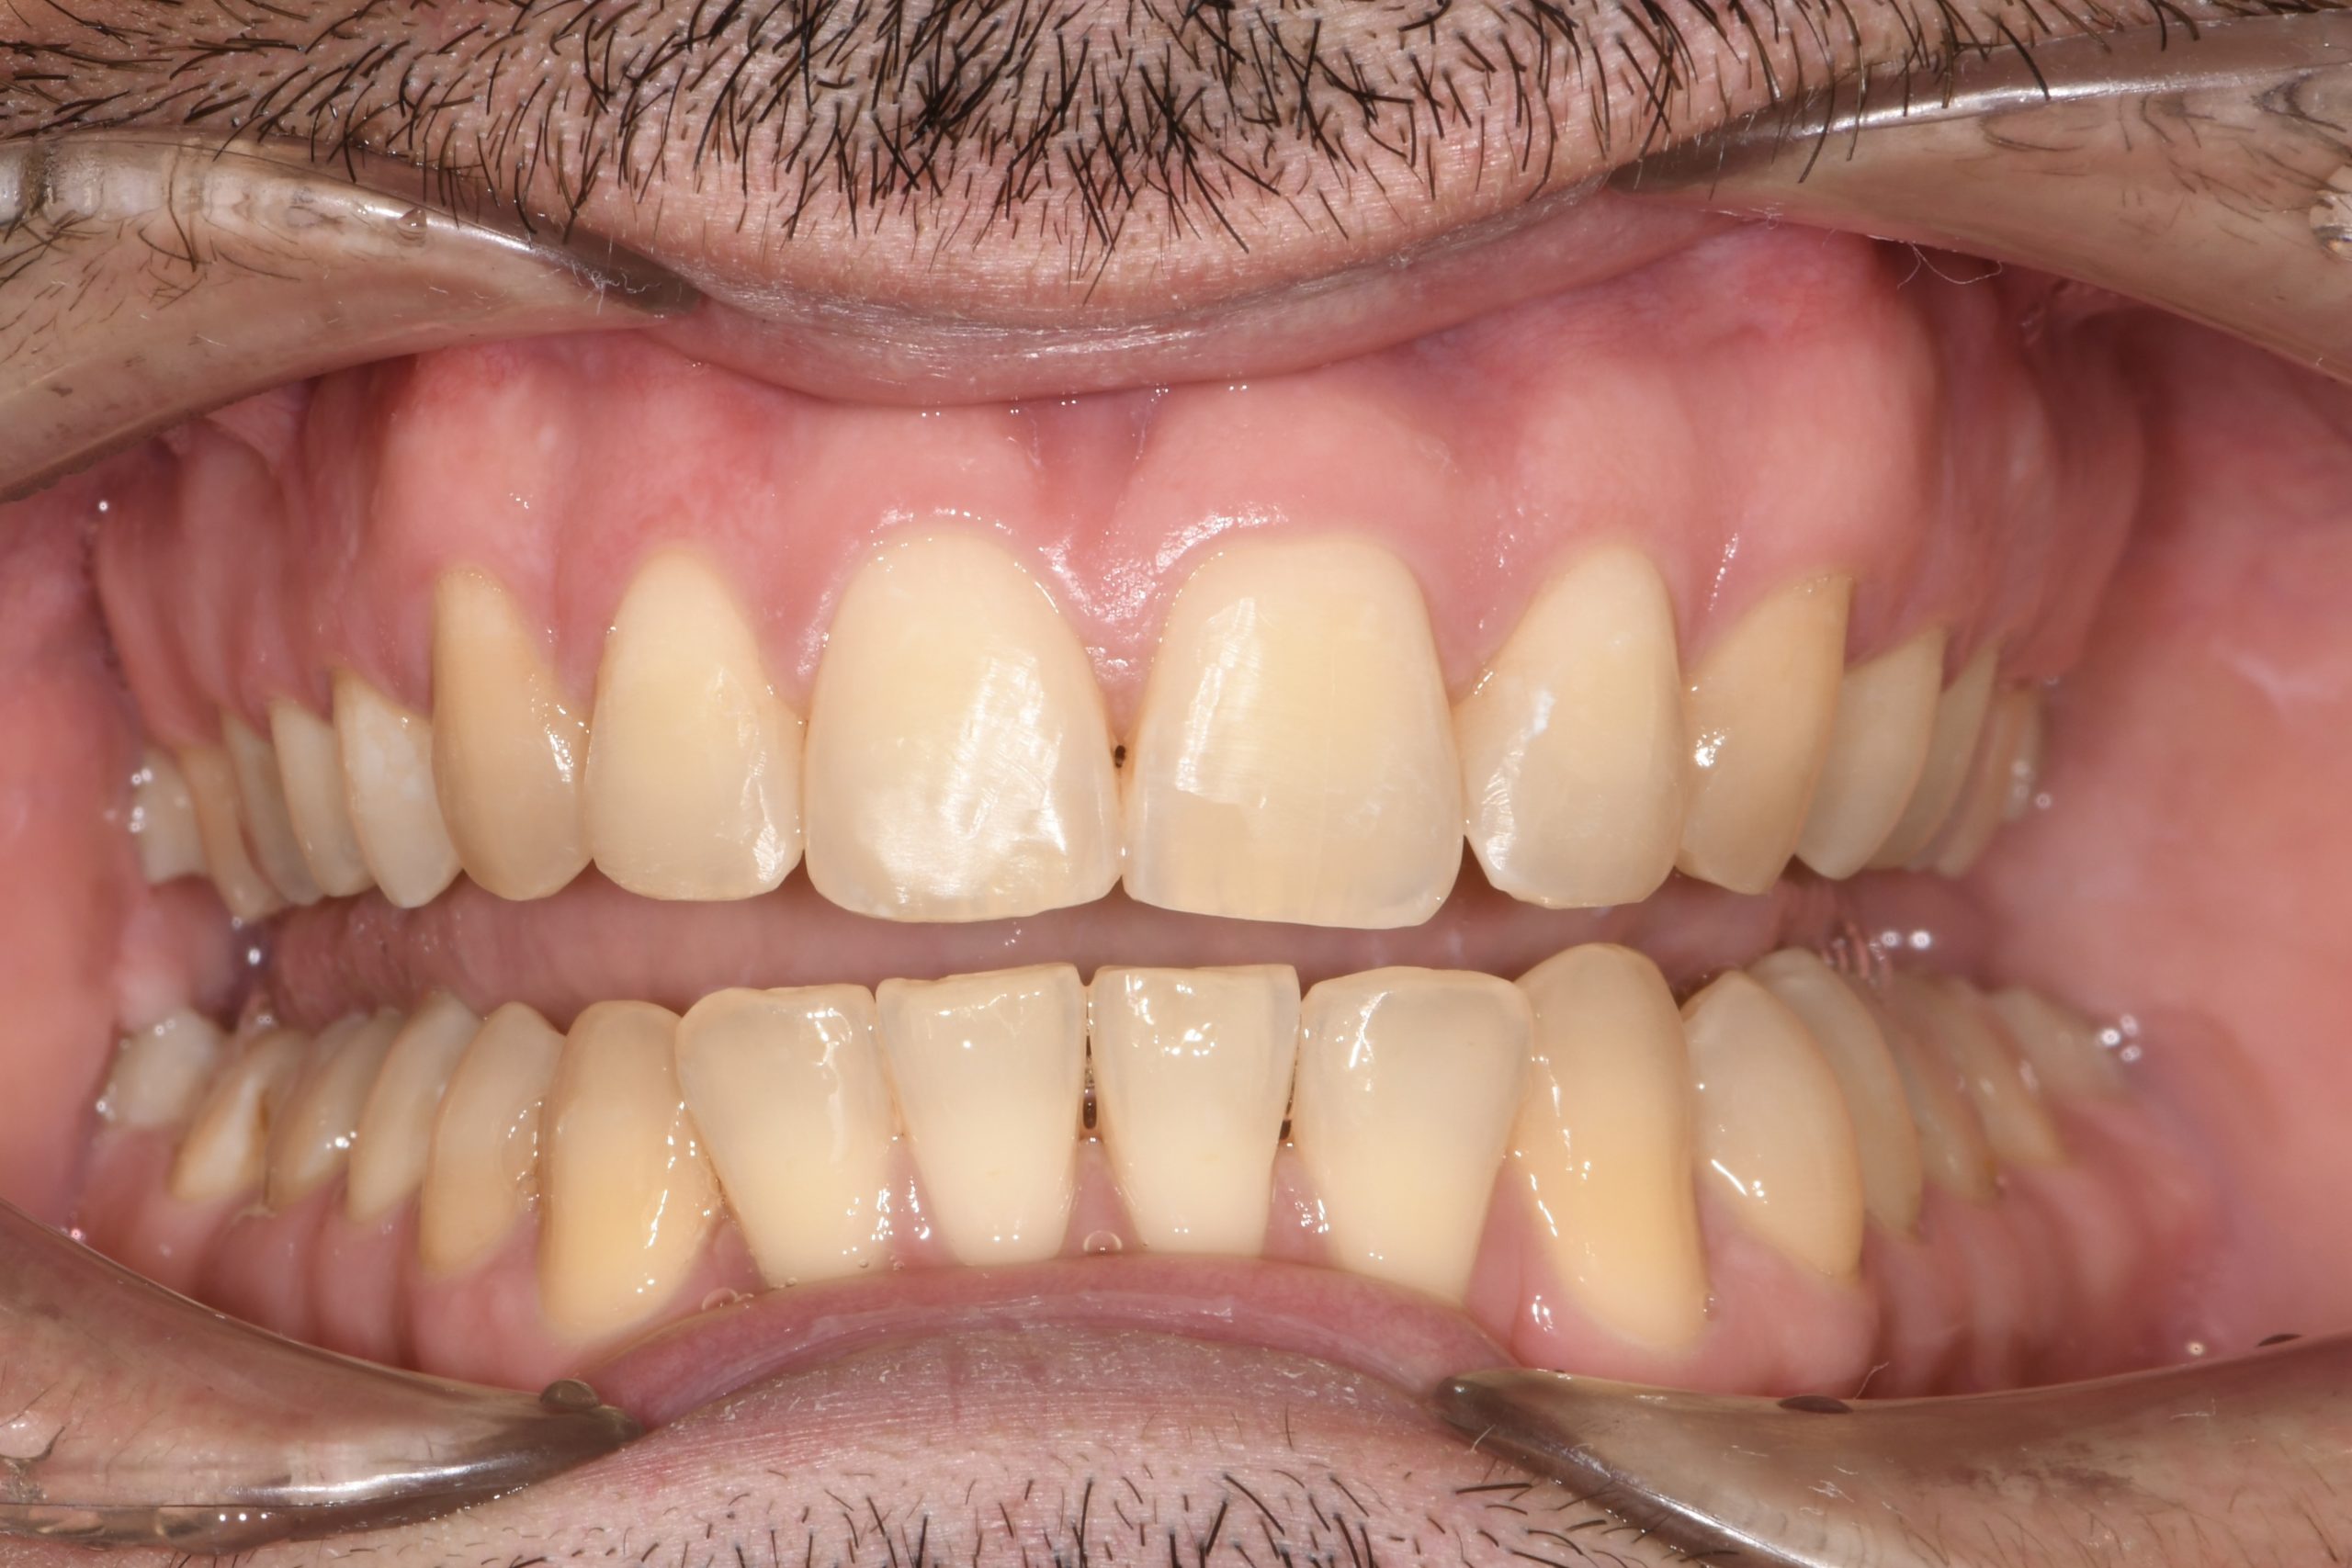

Az elmúlt évekből rengeteg szakmai referenciát tudnánk bemutatni, amelyek különböző fogszabályozási problémákat oldottak meg. Válogatva a több száz esetből, ezen az oldalon olyan képeket, információkat igyekeztünk bemutatni, amelyeknek a segítségével a jövőbeni pácienseinknek azt tudjuk üzenni: A Te fogsorod is lehet gyönyörű!

(Képeket a Pácienseink külön írásos beleegyezésével mutatjuk be!)